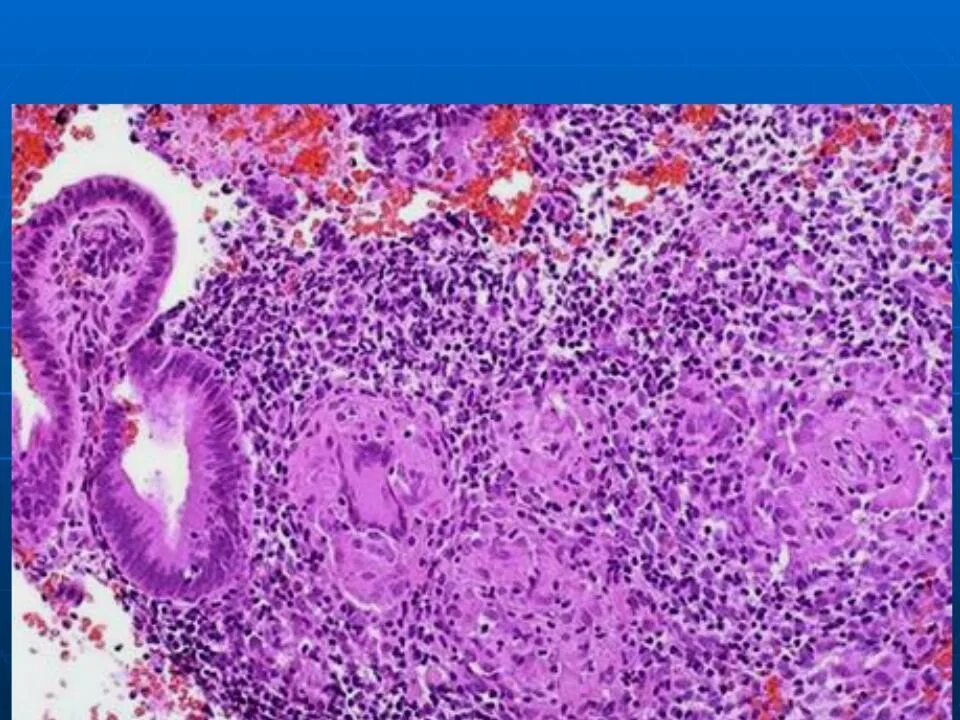

Эндометрит гистология